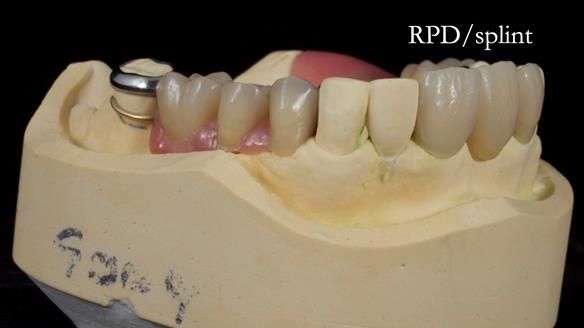

This edition features the case of Edgar, who sought help for a poorly fitting, acrylic-based partial denture that rocked, affected his speech, and caused discomfort. After considering various treatment options, including dental implants, Edgar opted for a metal-based removable partial denture, designed by myself with input from my technician, Rowan Garstang.

Treatment Process: I provided the clinical work while Rowan Garstang delivered the technical aspects. The treatment required fifteen visits to fit and review Edgar.